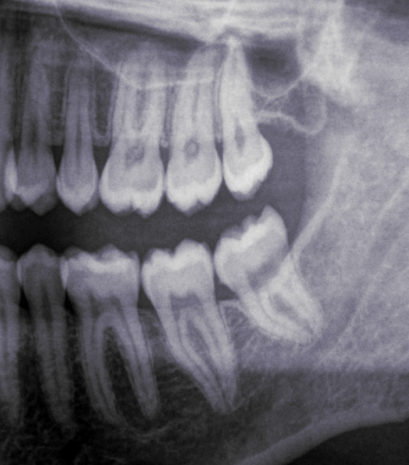

Look at these x-rays:

This patient was a female in her mid-30s. We will call her FA. As you can see, she only keeps her left wisdom teeth. At the age of 15, FAâs dentist wrongly diagnosed all her four wisdom teeth as impacted and recommended her to get them all out. FA was scheduled for two appointments: one to remove her right ones, and the other for the left ones.

Her left wisdom teeth, also diagnosed as impacted back then, are obviously not impacted! Having examined her mouth, I can confirm they are perfect, ideally erupted and taking part in chewing like the normal teeth they are. Yet, they were diagnosed as impacted, with no place and problematic. This is nothing short of horrifying.

And I can very confidently say that her right molars were not impacted either, because of her wide retromolar spaces to the right (that is, the spaces behind her second molars), because we can be sure that her dentist was not able to properly diagnose impactions, and because of how ideally positioned and erupted her remaining wisdom teeth are. And no, she wasnât having any kind of symptoms, discomfort or infections. Nor did she need the removal for any orthodontic or surgical reasons.